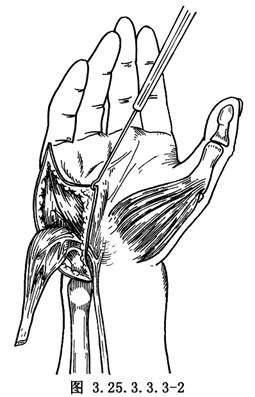

向尺側翻轉皮瓣,顯露小魚際肌,可見外展肌位於表層尺側,止於小指近節指骨基底部及部分腱膜與伸指腱膜連續。遊離切斷止點腱膜,儘量向遠側延伸,以免長度不夠。逆行遊離肌腹,直至切斷在豌豆骨上的尺側半起點,營養血管及支配神經位於肌腹近端橈側面應注意保護(圖3.25.3.3.3-2)。